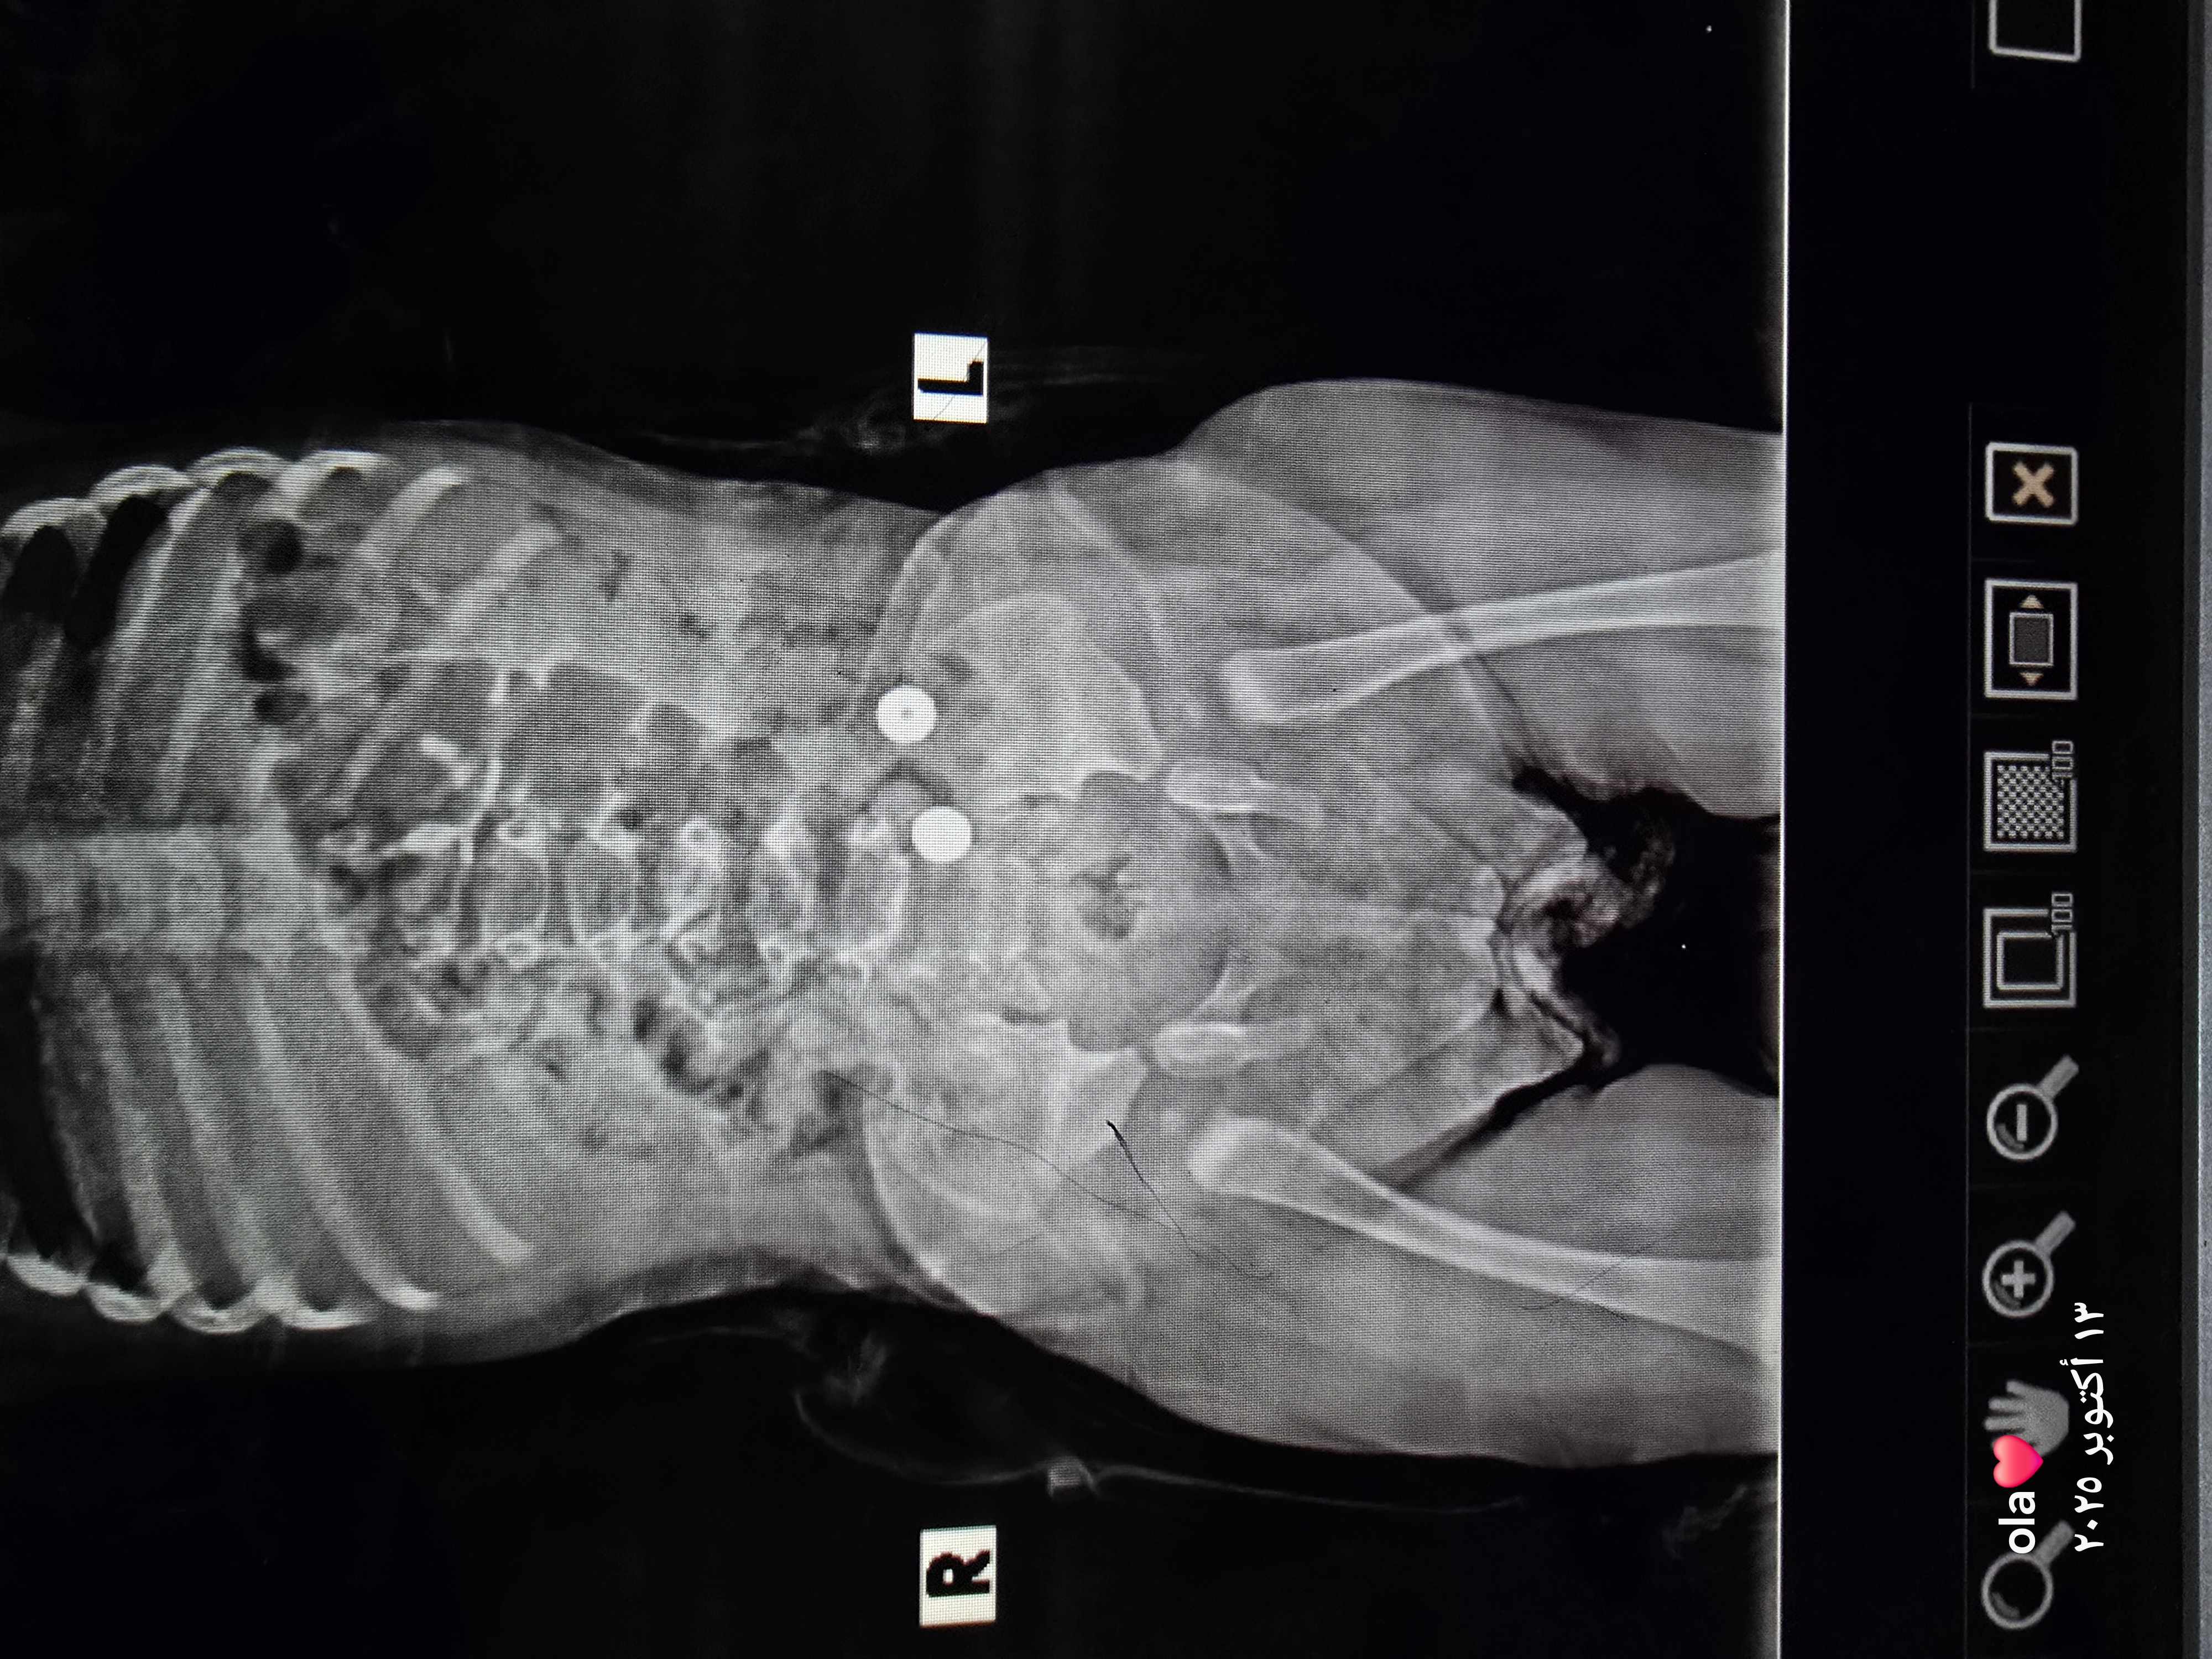

هل يوجد خلع ولادة في الصورة ام لا؟

شاهدت الصورة

وهي متناظرة و جيدة

ولا أشاهد علامات خلع ورك صريحة

ولو ان هناك تسطح بسيط في جوف المفصل الايمن

والافضل إعادة الصورة بعد عدة أشهر قبل بدء المشي